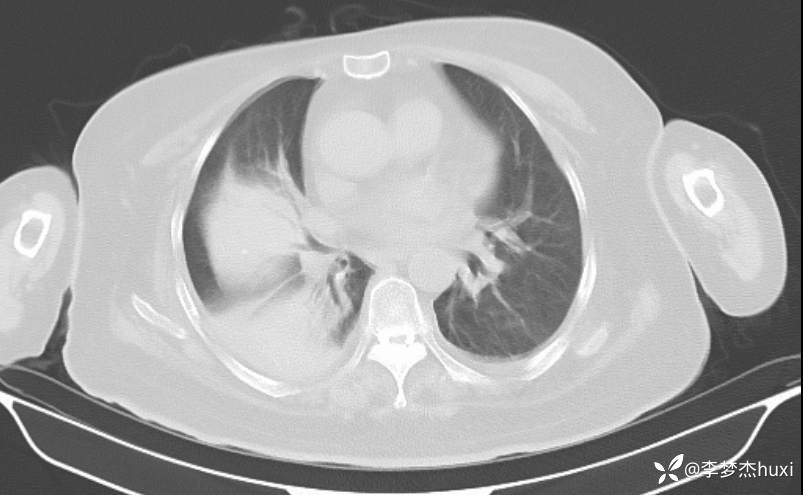

1.发热 待查 2.肺不张。